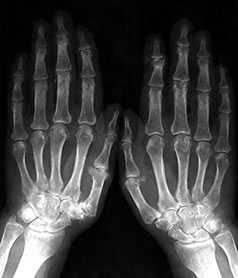

Умеренно выраженные или крупные остеофиты, деформация краев суставных поверхностей, значительное сужение суставных щелей, остеосклероз (узелки Гебердена в дистальных межфаланговых суставах и узелки Бушара в проксимальных), кисты со склеротическим ободком, краевые дефекты суставных поверхностей, при этом костные выступы с одной стороны могут вклиниваться в другую. Обычно краевые дефекты окружены зоной остеосклероза (рис. 3).

Рис. 3. Обзорная Rо-графия кистей.

Множественные артрозы дистальных и проксимальных межфаланговых суставов. Множественные узелки Гебердена и Бушара. Выраженный артроз 1-го левого запястнопястного сустава